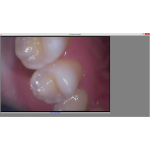

Imagens nítidas e cores reais

Iluminação LED superior

Resolução: 2 megapixéis

Sensor de imagem: CMOS

Distância focal: 10 mm ~ 40 mm

Fonte de luz: 6 LEDs brancos